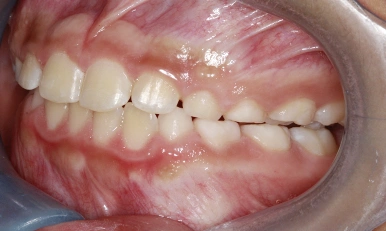

Patient Results